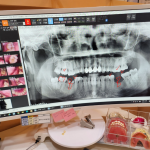

Unday bo'lsa sizga yuqori sifatli Implant xizmatini taklif qilamiz nima uchun ayna biz deysizmi? 10yillik tajribaga va butun Korea bo'ylab TOP5 talikga kiruvchi do'ktorlar sizga xizmat qiladi

Yuqori tajriba baribir o'z foydasini ko'rsatmay qolmaydi shunday ekan siz xoxlagan natijaga erishish uchun sizga albatta yuqori tajribali doktorlar yordami kerak boladi shunay ekan biz shu yerdamiz!